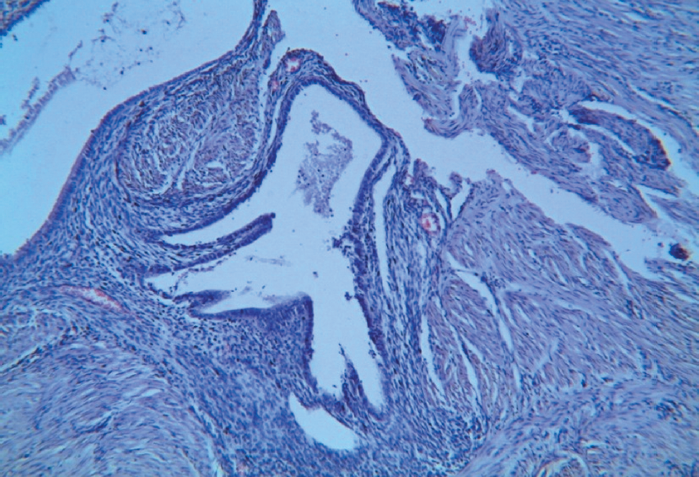

- Лейомиомы с очагами эндометриоза (рис. 4, 5). 2. Очаги эндометриоза между пучками гладкомышечных волокон (рис. 3). 3. Лютеиновая киста яичника.

Рис. 3. Склеротическая форма аденомиоза. Между пучками гладкомышечных волокон участки эндометриоза. Окраска гематоксилином и эозином. Увеличение ×10

Fig. 3. Sclerotic type of adenomyosis. Endometriosis lesions are recognized surrounding smooth muscle fibers with bundled growth pattern. Haematoxylin and eosin stained specimens. ×10 magnification